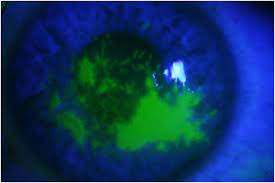

Two principal forms are recognized: 13 hsv epithelial keratitis is the result of the virus' destruction of corneal epithelial cells secondary to viral replication. The hallmark of hsv keratitis is the presence of multiple small branching epithelial dendrites on the surface of the cornea, although often times it first presents as a coarse, punctuate epithelial keratitis (and may be mistaken for a viral keratitis). The most common type of eye herpes is called epithelial keratitis. May be single or multiple, with typical terminal bulb at the tips of dendrite branches.

In uk, responsible for 1 in 10 corneal transplants Research suggests combining both oral antiviral and topical therapy is not necessary in the treatment of epithelial hsvk. The hallmark of hsv keratitis is the presence of multiple small branching epithelial dendrites on the surface of the cornea, although often times it first presents as a coarse, punctuate epithelial keratitis (and may be mistaken for a viral keratitis). Epithelial keratitis caused by herpes zoster manifests in two ways. Erpes simplex virus (hsv) stromal keratitis is the leading infectious cause of corneal blindness in developed nations.

Epithelial keratitis caused by herpes zoster manifests in two ways. Two principal forms are recognized: Hsv keratitis (hsvk) is the most common cause of corneal blindness in developed nations. Research suggests combining both oral antiviral and topical therapy is not necessary in the treatment of epithelial hsvk. Outlook eye herpes, also known as ocular herpes, is a condition of the eye caused by the herpes simplex virus (hsv). Gentle epithelial debridement may be performed to remove infectious virus and viral antigens that may induce stromal keratitis. A controlled trial of oral acyclovir for the prevention of stromal keratitis or iritis in patients with herpes simplex virus epithelial keratitis. The hallmark of hsv keratitis is the presence of multiple small branching epithelial dendrites on the surface of the cornea, although often times it first presents as a coarse, punctuate epithelial keratitis (and may be mistaken for a viral keratitis). In uk, responsible for 1 in 10 corneal transplants Herpes simplex virus (hsv) is associated with a variety of ocular diseases, including epithelial and stromal keratitis. A controlled trial of oral acyclovir for the prevention of stromal keratitis or iritis in patients with herpes simplex virus epithelial keratitis. Erpes simplex virus (hsv) stromal keratitis is the leading infectious cause of corneal blindness in developed nations. Many factors have been attributed to this clinical phenomenon.